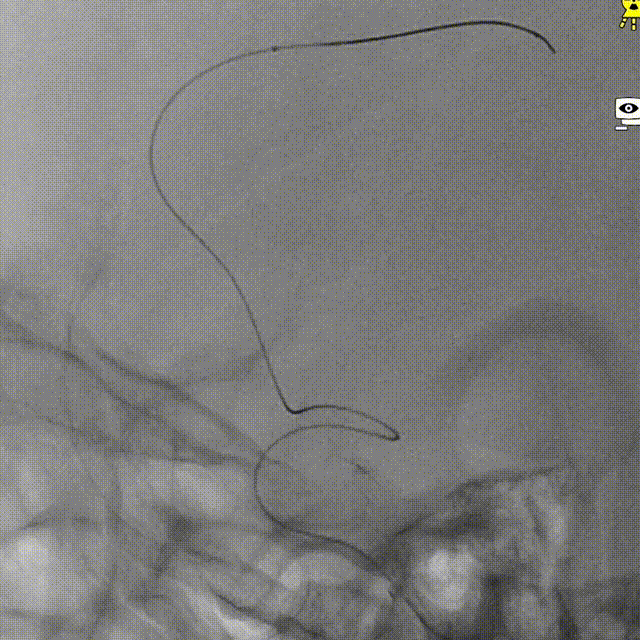

支架到位。

支架全段打开。

支架全段打开造影。

术后造影。

术后正侧位造影。

术后VASO CT。

强易达(Choydar)血流导向密网支架材质是镍钛合金,输送易到位;头端导丝、50%释放点、100%释放点清晰,便于观察支架位置。

支架由2对4根铂钨合金显影丝以对向排列的方式,混合编入支架主体,呈3D立体显影效果,便于观察支架贴壁情况。